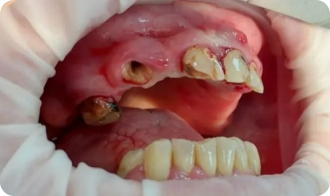

Установка All-on-4

До приёма:

• Полная адентия зубов

• Атрофия костной ткани

Результат:

• Установка имплантов Osstem

• Костная пластика

Срок: 2 дня